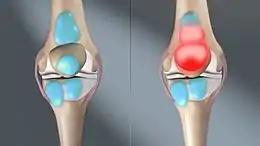

Bursitis is inflammation or swelling of one or more fluid filled sacs known as bursae.[3] These sacs are lined with a synovial membrane that produce a lubricating synovial fluid.[4] With bursitis there may be difficulty moving, tenderness, and pain in the area affected.[1] With bursitis of gradual onset pain may be absent.[3] Complications may include septic bursitis.[2]

Bursitis commonly affects superficial bursae. These include the subacromial, prepatellar, retrocalcaneal, and pes anserinus bursae of the shoulder, knee, heel and shin, etc. (see below).[4] Symptoms vary from localized warmth and erythema[4] to joint pain and stiffness, to stinging pain that surrounds the joint around the inflamed bursa. In this condition, the pain usually is worse during and after activity, and then the bursa and the surrounding joint becomes stiff the next morning.

Traumatic injury is another cause of bursitis. The inflammation irritates because the bursa no longer fits in the original small area between the bone and the functionary muscle or tendon. When the bone increases pressure upon the bursa, bursitis results. Sometimes the cause is unknown. It can also be associated with various other chronic systemic diseases.